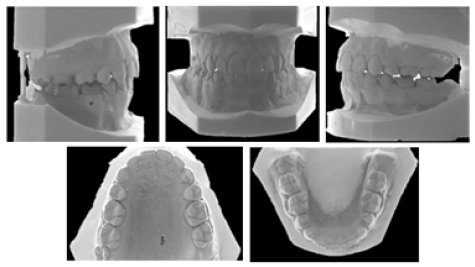

The post-treatment facial photographs showed that the patient was satisfied with the outcome of facial aesthetics. Macro esthetics and micro esthetics were achieved (Figure 7). Lip muscle activity was a little bit high and there was also an acceptable mental muscle hyperactivity. Normal overjet and overbite relationships were achieved. The skeletal class II relationship was corrected, mandibular autorotation was obtained, leveling and alignment was achieved, and a balanced occlusion was obtained (Figure 8). Open bite was corrected, normal incisal relationship and normal canine guidance were obtained. The outcome of posttreatment panoramic graph displayed an acceptable root parallelism (Figure 9). No sign of root resorption was evident. Retention was done both by canine to canine bonded fixed retainer and a vacuum formed retainer (VFR). Facial, dental esthetics, and dental stability mostly maintained during the 5-year retention period (Figure 4 & 10). There are some changes in occlusion (mild relapse) but patient remained without any symptom during the post-treatment period.

Figure 8:Post-treatment dental casts.